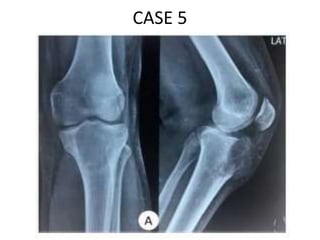

CASE 5